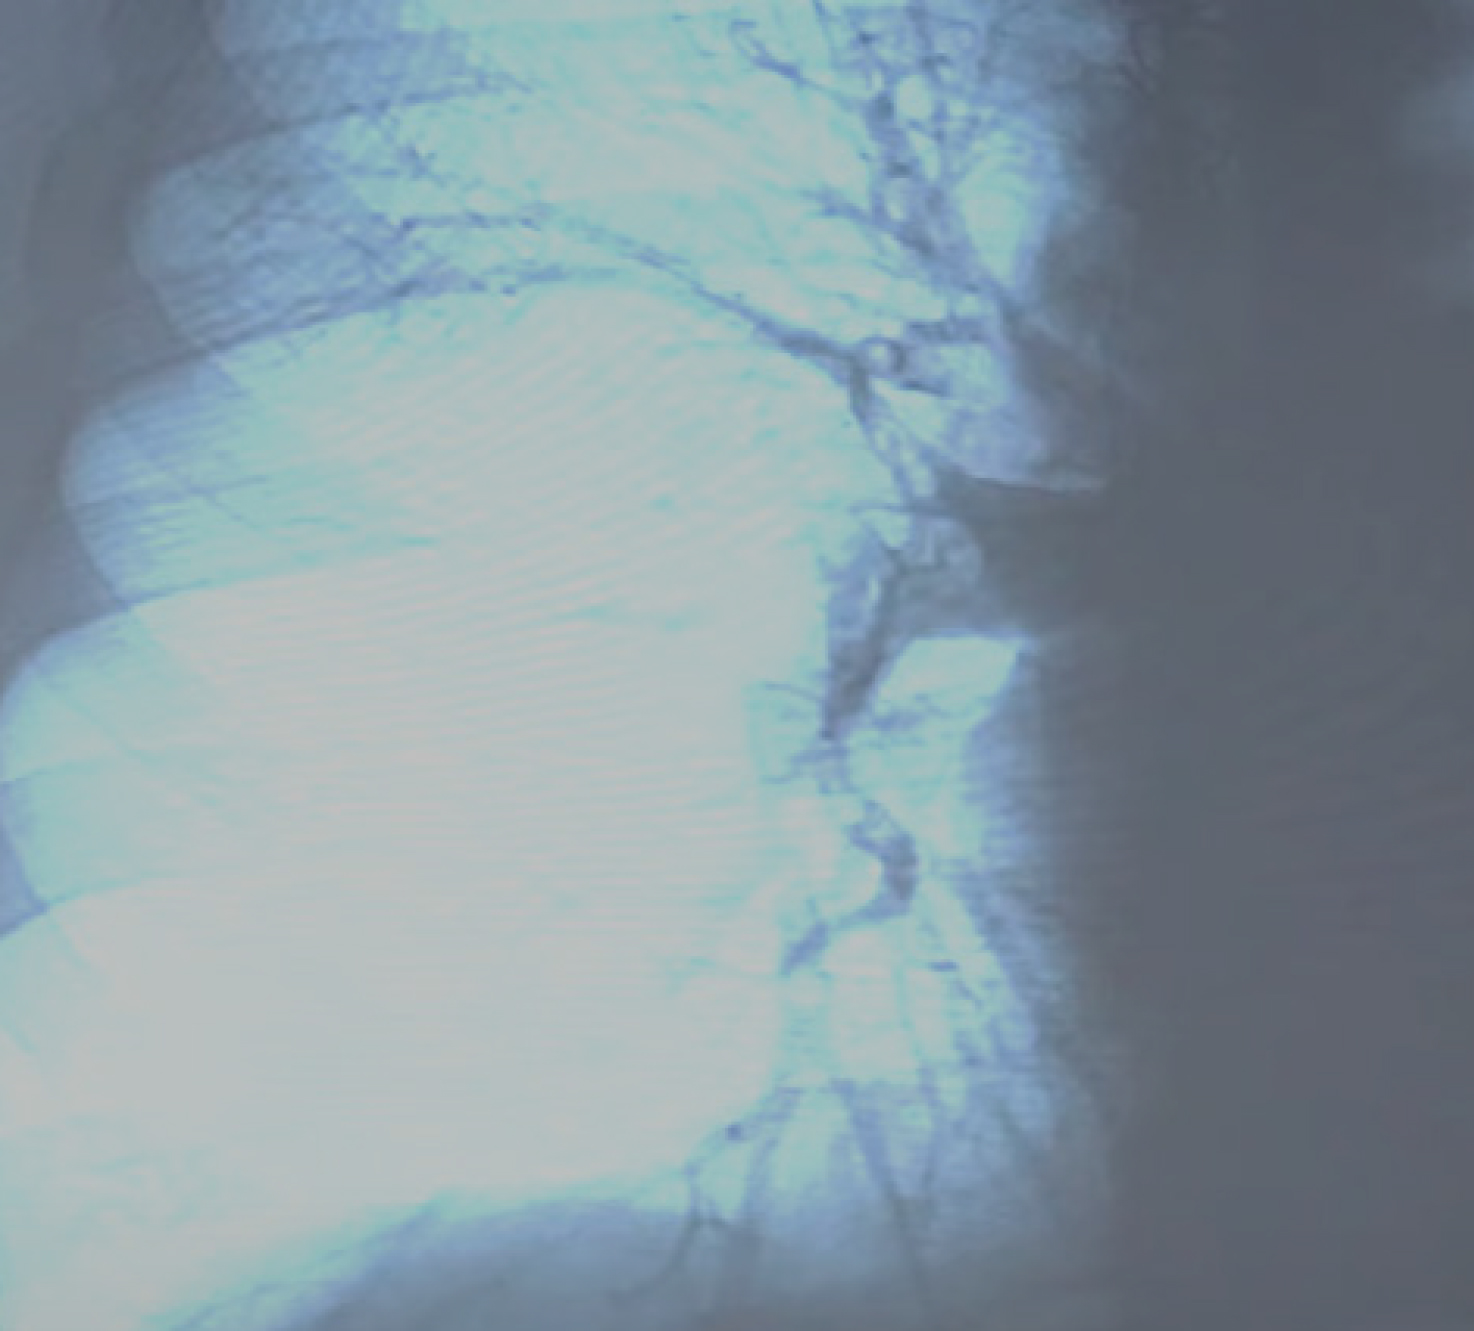

Лечение. В рентгенэндоваскулярной операционной экстренно проведена ангиопульмонография (рис. 2). Была проведена попытка селективного тромболизиса с учетом наличия флотирующего тромба в глубокой бедренной артерии. По данным прямого измерения давления в легочной артерии легочная гипертензия регрессировала, по данным контрастирования проходимость легочной артерии восстановлена. Системный тромболизис не применялся с целью высокого риска повторной тромбоэмболии. Также с целью защиты от повторной тромбоэмболии проведена установка съемного кава-фильтра.

Рис. 2. Ангиопульмонография, картина среднедолевой эмболии в системе правой легочной артерии